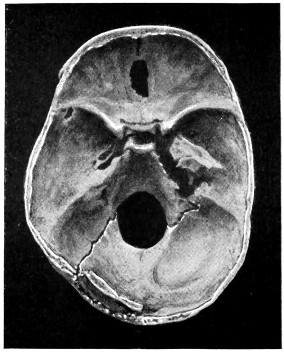

| 50 A and B. The inner aspect of the skull and the same seen on transillumination | 137 |

| 51. To illustrate compression of the brain as produced by an extra-dural hæmorrhage from the middle meningeal artery[x] | 141 |